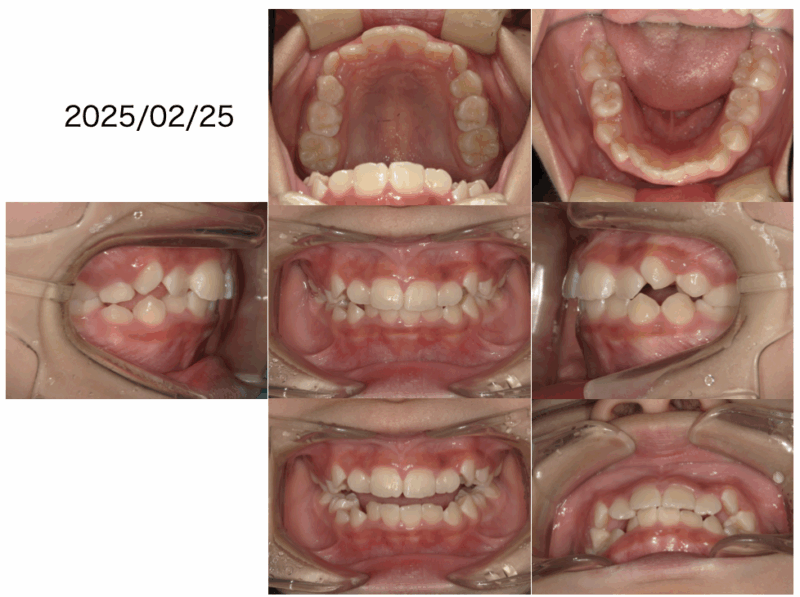

凸凹改善2025年10月21日Written by 土持歯科クリニック主訴は凸凹でした。お口を開けてる状態を見ると上下のバランスも悪いです。原因は口呼吸です。まずは鼻呼吸に改善しましょう。鼻呼吸に変わったことで、少し良くなりました。下の前歯の凸凹と上顎の糸切り歯の隙間が足りません。次のトレーニングを始めました。トレーニングが上手くいってます。裏側から見えない装置で糸切り歯の隙間改善に取り掛かりました。一見綺麗に思えますが。上顎の歯が全部大人の歯に変わるまではトレーンーニングを親子で頑張ってください。